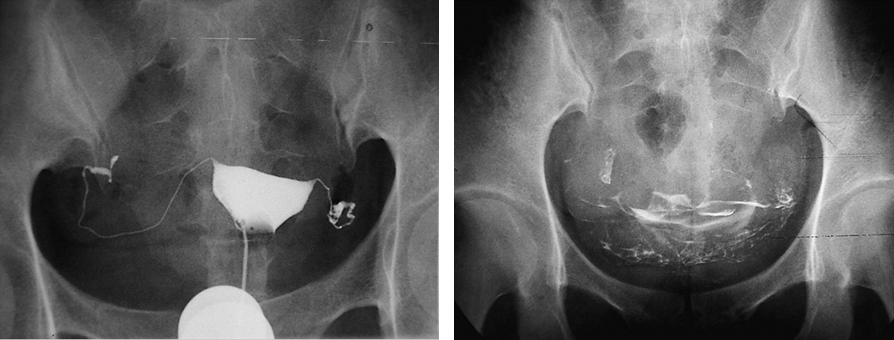

(3)输卵管通畅检查:子宫输卵管造影是评价输卵管通畅度的首选方法。应在月经干净后3~7日无任何禁忌证时进行。既可评估宫腔病变,又可了解输卵管通畅度。

子宫输卵管碘油造影片 子宫输卵管碘油造影弥散片